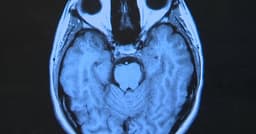

Scientists at Stanford University have detailed a mechanism by which mRNA COVID-19 vaccines may cause damage to heart cells, leading to myocarditis. The research indicates that elevated levels of certain immune proteins in vaccinated individuals experiencing this rare complication prompt neutrophils, a type of immune cell, to infiltrate heart muscle tissue, resulting in inflammation and damage.

This study analyzed blood samples from patients who developed myocarditis after vaccination, identifying proteins like CXCL10 and IFN-gamma. Subsequent experiments in mice demonstrated that these proteins could indeed trigger neutrophil infiltration in the heart. While myocarditis following vaccination is generally mild and resolves on its own, this research provides a clearer understanding of its biological underpinnings.